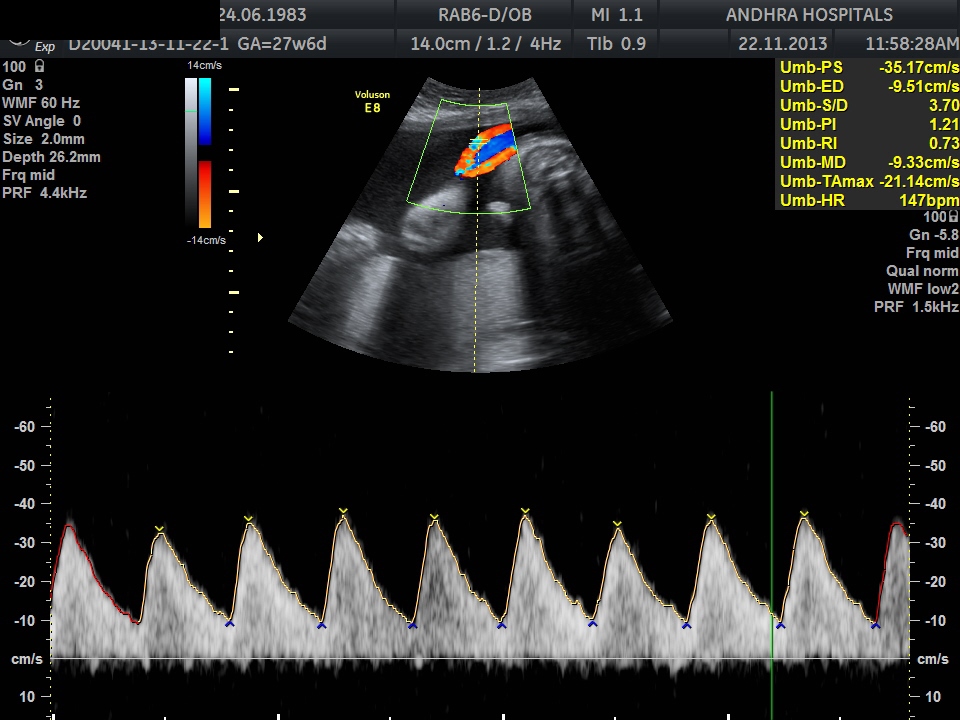

3D Anomaly

Caption for the second image.